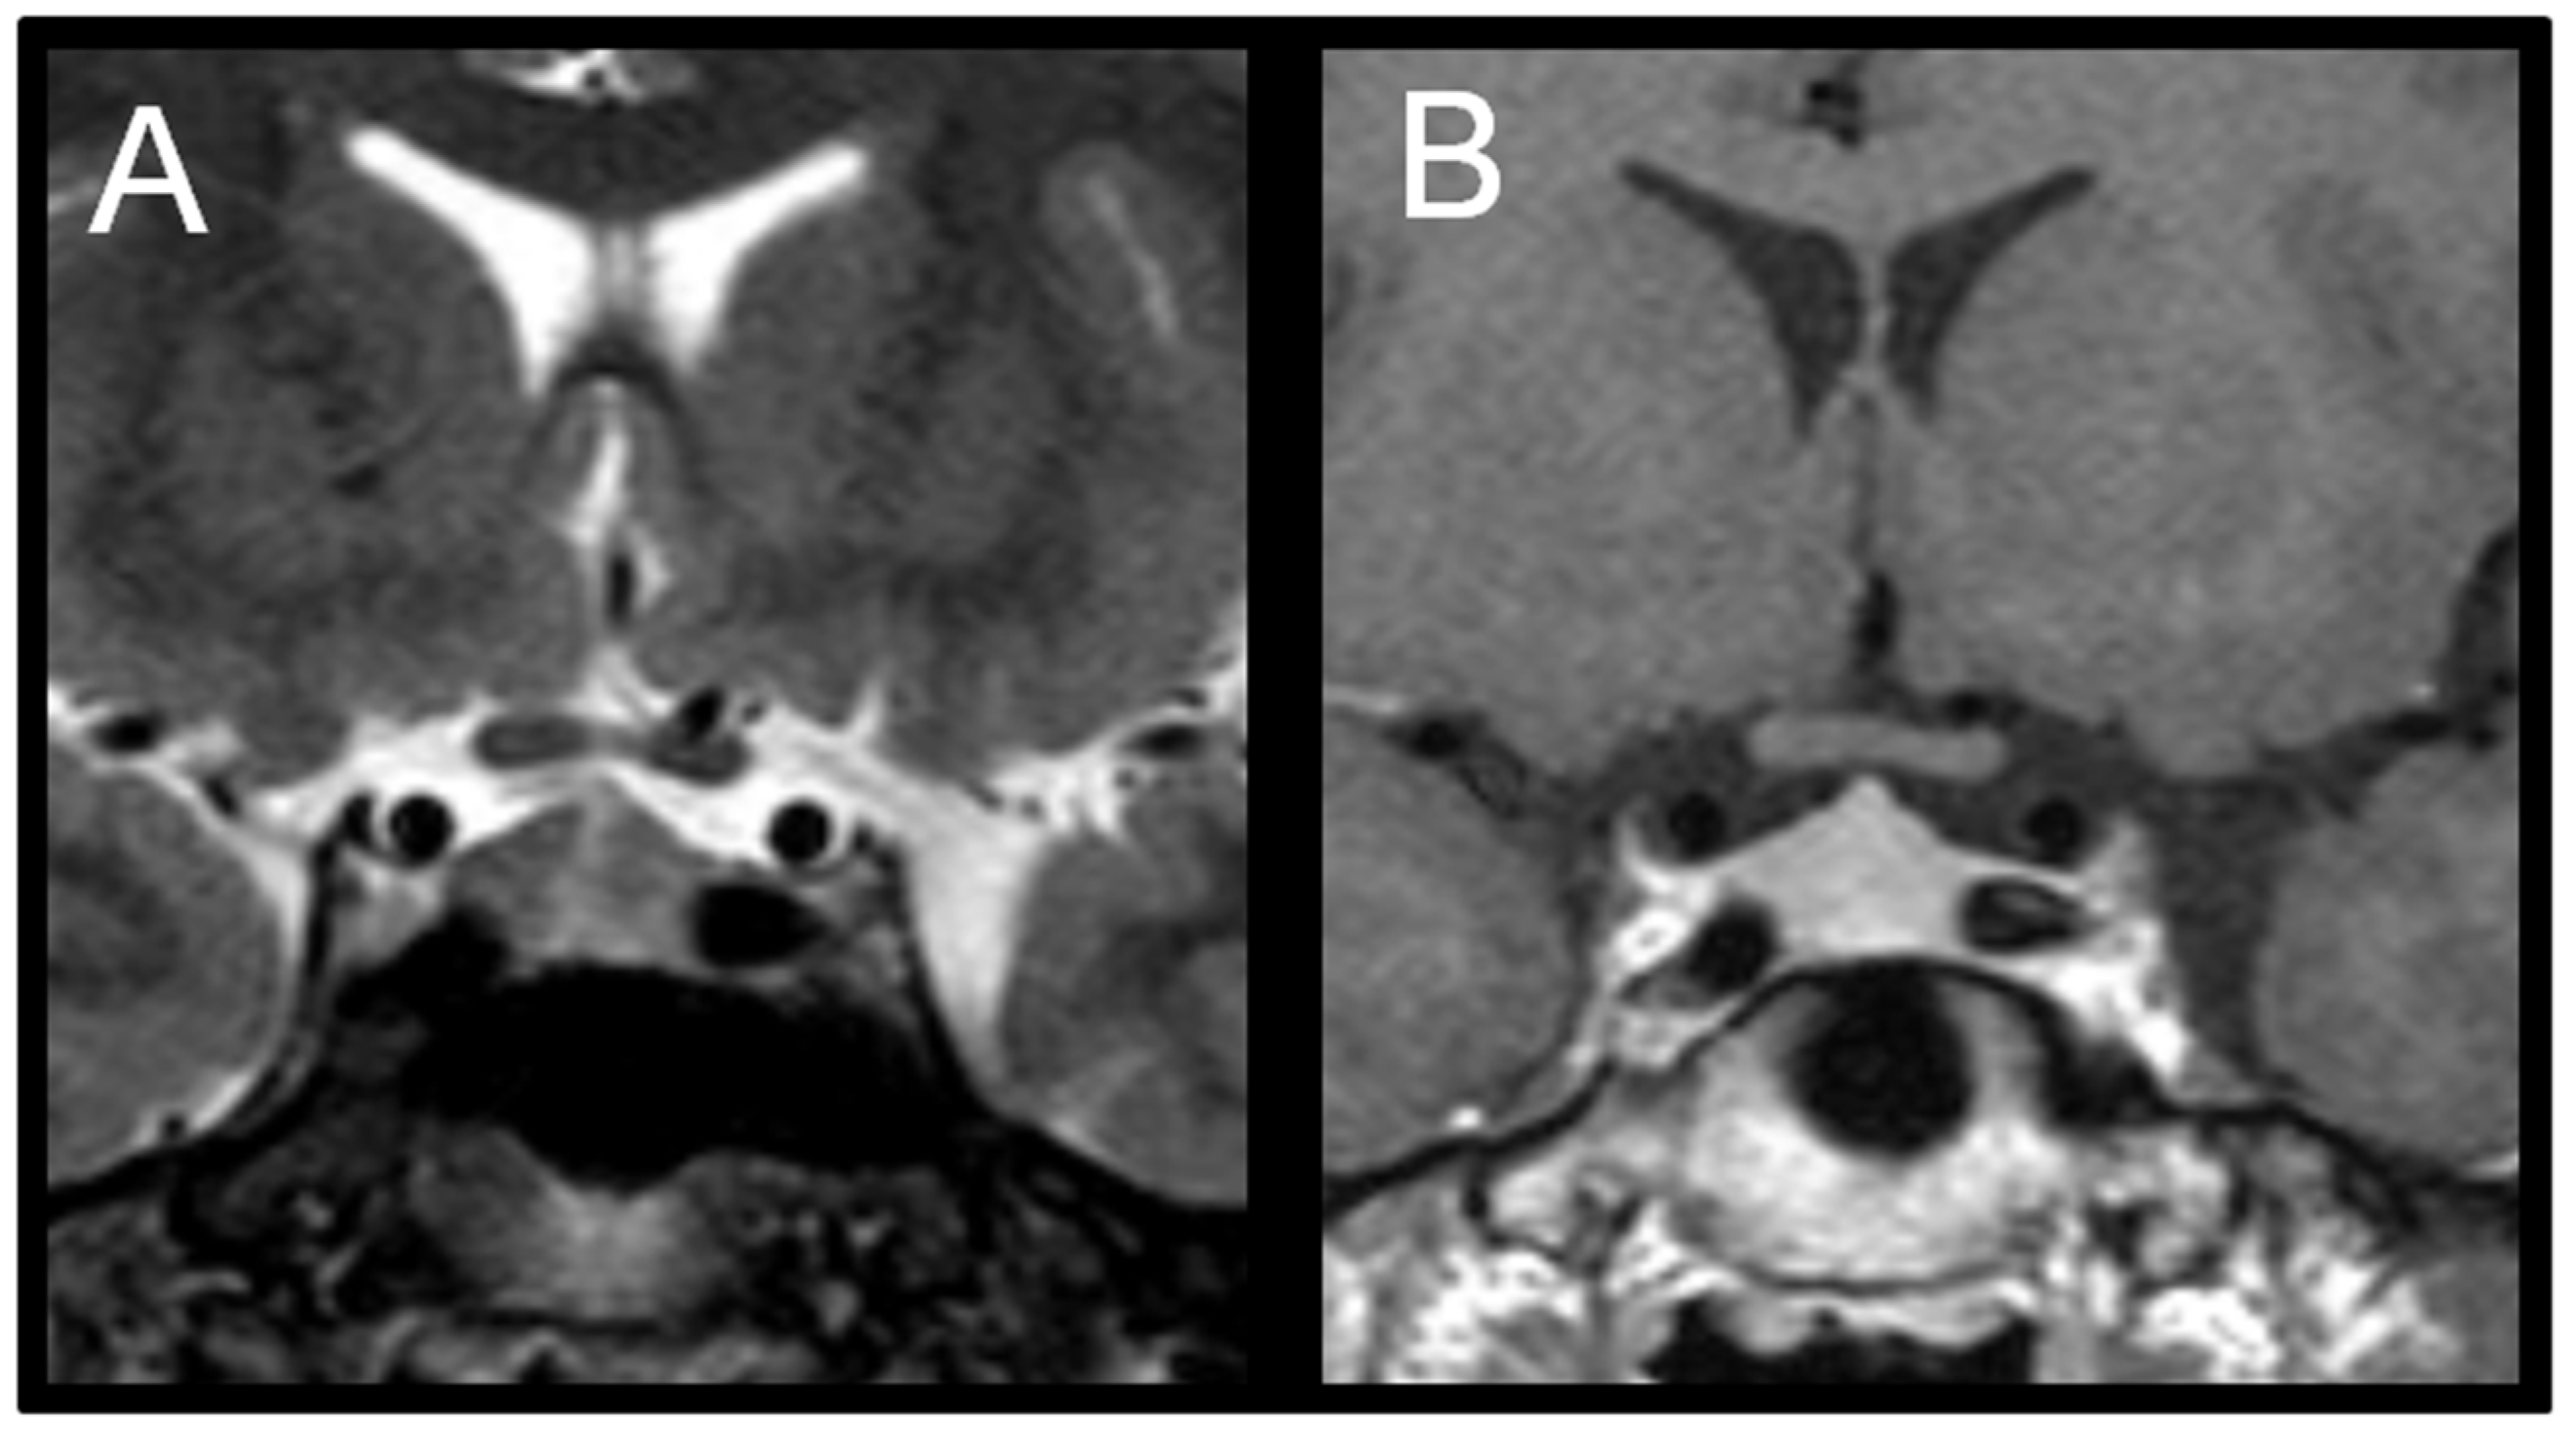

Because gonadotropins remained elevated, a pituitary MRI was repeated at the 24-month-follow-up (T24), which revealed an enlarged pituitary gland measuring 10 mm in height with superior convexity approaching suprasellar cistern, suggestive of reactive pituitary hyperplasia (Figure 2).

Figure 2. (A) Coronal T2-weighted image shows symmetric enlargement of the pituitary gland. (B) Coronal T1-weighted post-contrast image shows homogeneous enhancement; maximum height of pituitary gland is about 10 mm.